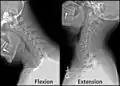

Radiographie de la colonne cervicale en flexion et en extension.